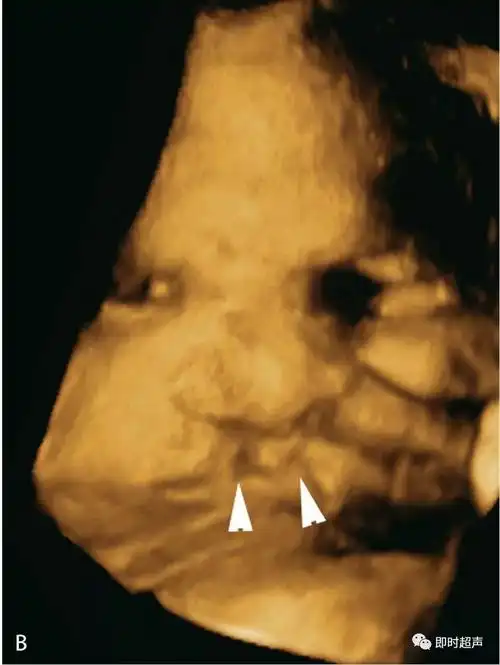

(b)同一胎儿的三维图像显示双侧唇裂(三角箭头).图6.1.